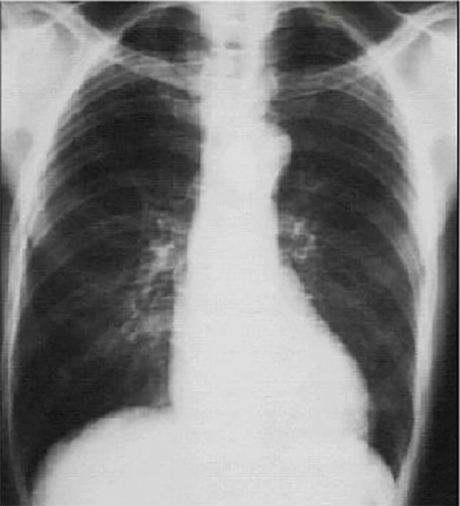

PA

Click on the xray to enlarge it.

Not routine exam in hypertension

Choose the best interpretation of the chest X ray:

Left ventricular enlargement

and left atrial enlargement

Prominent aortic knob

Rib notching

Dilated ascending aorta

Left ventricular enlargement and a dilated aorta